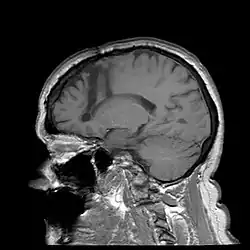

Lobotomia przedczołowa, zwana także lobotomią (z gr. λοβός (lobos) 'płat', i τομή (tomē) 'cięcie, sekcja') lub lobotomią czołową[1] albo leukotomią przedczołową[2] – zabieg neurochirurgiczny polegający na przecięciu połączeń kory przedczołowej z innymi strukturami mózgowia, jedna z pseudonaukowych metod leczenia chorych na schizofrenię i inne ciężkie choroby psychiczne[3][4][5].